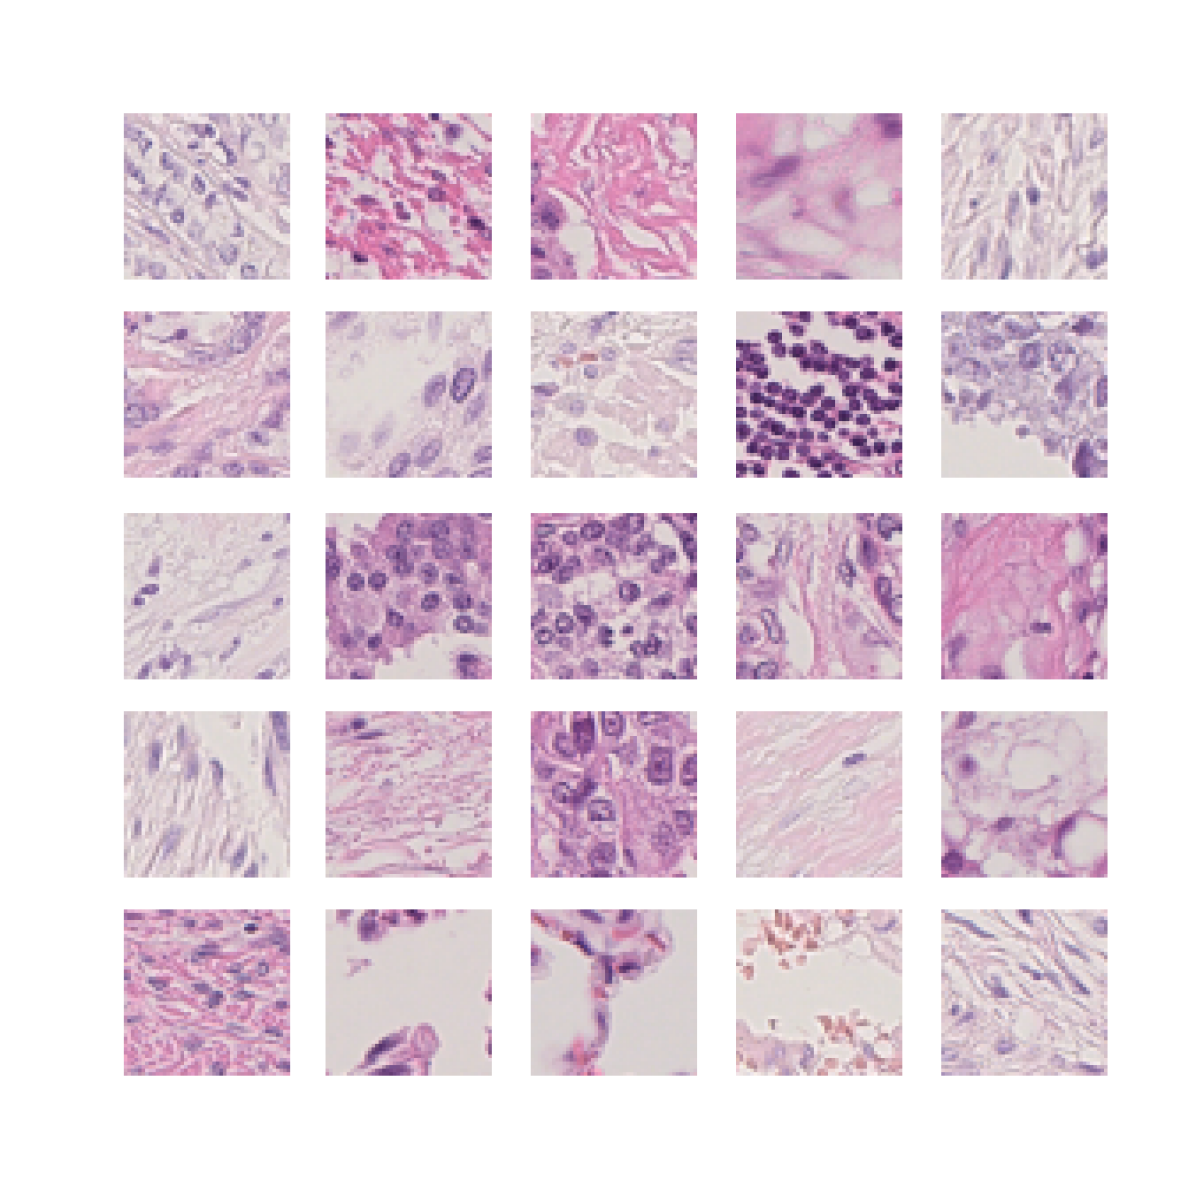

We also analyse the activation maps for each model using GradCAM as described in section S3. This offers more insight into the areas of the image which are contributing most heavily to the models’ representations. In Figure 4(b) we present some representative examples, however, a larger selection which was chosen at random is presented in Figures S10 to S25. The larger selection makes it easier to see the emergent patterns, including that privileged Siamese models tend to mainly identify features which are strongly present in both inputs, while unprivileged Siamese models tend to learn more diffuse features that are not specific to one cell phenotype or image region. TriDeNT ♆ incorporates both sets of features, learning both features specific to the privileged data and more the general features associated with unprivileged Siamese networks.

We can see in Figure 4(b) panel A that for ERG, the privileged Siamese model focuses almost exclusively on any nuclei which could be endothelial cells. As there are very few endothelial cells in the dataset, it could be an effective strategy to identify anything that could potentially be an endothelial cell to minimise the difference between the representations of the H&E model and the IF mask model. In the corresponding unprivileged Siamese image, we see that the model identifies some of these nuclei, albeit less strongly, but also focuses heavily on the other tissue and even the background, while strongly fixating on two spots of debris in the center of the image. This model has less ‘incentive’ to learn the weak features related to endothelial cells as these occur rarely and are not easy to detect, while more generic strong features such as the presence of connective tissue and the prevalence of background are more common and predictable from augmented images. We see that TriDeNT ♆ combines these two feature sets, strongly identifying nuclei while also identifying the connective tissue.

In panel C we see a similar pattern, with the privileged Siamese model fixating solely on the nuclei, while the TriDeNT ♆ model takes a more balanced approach. The unprivileged Siamese model appears to focus on a single cluster of nuclei while neglecting others, and similarly identifies an area of fibroblasts with its distinctive pattern but does not others.

In contrast to panels A and C which represent models with poor privileged Siamese results, panels B and D represent models whose privileged Siamese results were comparable to both TriDeNT ♆ and even the supervised baseline. It is therefore interesting to note that there are far more similarities between the privileged Siamese and TriDeNT ♆ models in both cases. Particularly in panel B, TriDeNT ♆ and the privileged Siamese model return virtually identical heatmaps, with both strongly identifying epithelial nuclei and neglecting the same areas of connective tissue. The unprivileged model in this case appears to focus solely on the centre of the image, giving a significantly different heatmap to the other panels.

Panel D again shows the previous pattern, with the privileged Siamese model identifying the features strongly present in the privileged data – fibroblasts – while neglecting the nuclei present. TriDeNT ♆ also strongly identifies the connective tissue, but, unlike the privileged Siamese model, does not completely neglect the nuclei. The unprivileged Siamese model primarily identifies background, and does not appear to identify the nuclei in this example.